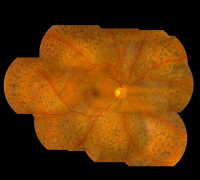

珠海希玛眼科医院:糖尿病视网膜病变,怎么办?

糖尿病患者视网膜病变在糖尿病患者中十分的广泛,患病率十分的高,而且会伴随着现病史的增加而迅速提升。糖龄超出三年的,发病率大概在5%;糖龄超出5年的已达25%;超出十年糖龄...